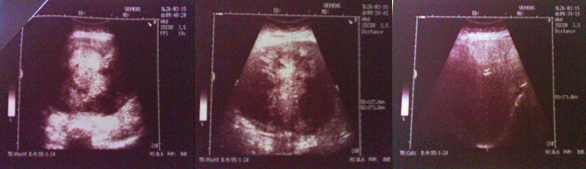

Ultrazvučnim pregledom utvrđeno je da je jetra blago uvećana, k-k promera 171mm, bez fokalnih lezija. U regiji pankreasa prisutna heterogena, najvećim delom hipoehogena, delimično i nekrotična Tu promena okvirnih dimenzija 173x137mm. Slezina, žučna kesa I bubrezi urednog ehonalaza (slika 1).

Slika 1. Ultrazvučni nalaz pacijenta.